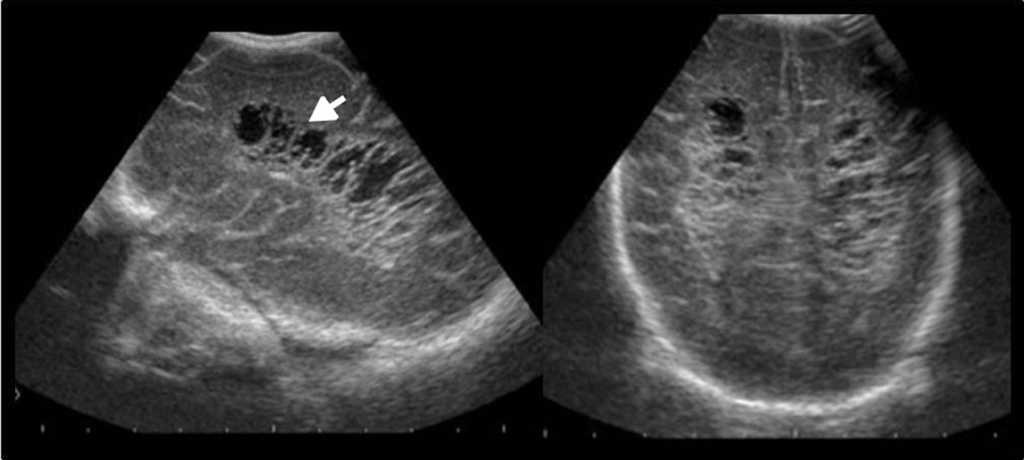

En cuanto a las patolog??as de la v??a biliar y vesicular, la ecograf??a es la t??cnica diagn??stica m??s efectiva. Adem??s de identificar f??cilmente cuadros de colecistitis aguda (fig. 7), valora la v??a biliar y distingue la etiolog??a liti??sica (fig. 8) o pancre??tica1,5.

El avance de la tecnolog??a asociado a los equipos de ultrasonido, m??s la mayor profesionalizaci??n, hacen posible en la actualidad el diagn??stico de patolog??as a nivel intestinal, incluyendo desde procesos agudos, como la apendicitis (figura 9) o diverticulitis, hasta patolog??as m??s complejas, como tumores intestinales, enfermedad inflamatoria intestinal o enfermedades infecciosas14,15 (figs. 10 y 11).

Para la exploraci??n del tracto gastrointestinal, se comienza utilizando el transductor curvil??neo de 3,5-5 MHz y luego se completa con uno lineal de alta frecuencia (5-12 MHz), que brinda muy buena definici??n de la pared intestinal y sus capas. A su vez, se realizan maniobras de compresi??n gradual con el transductor a fin de movilizar y desplazar las asas intestinales y el contenido a??reo14.